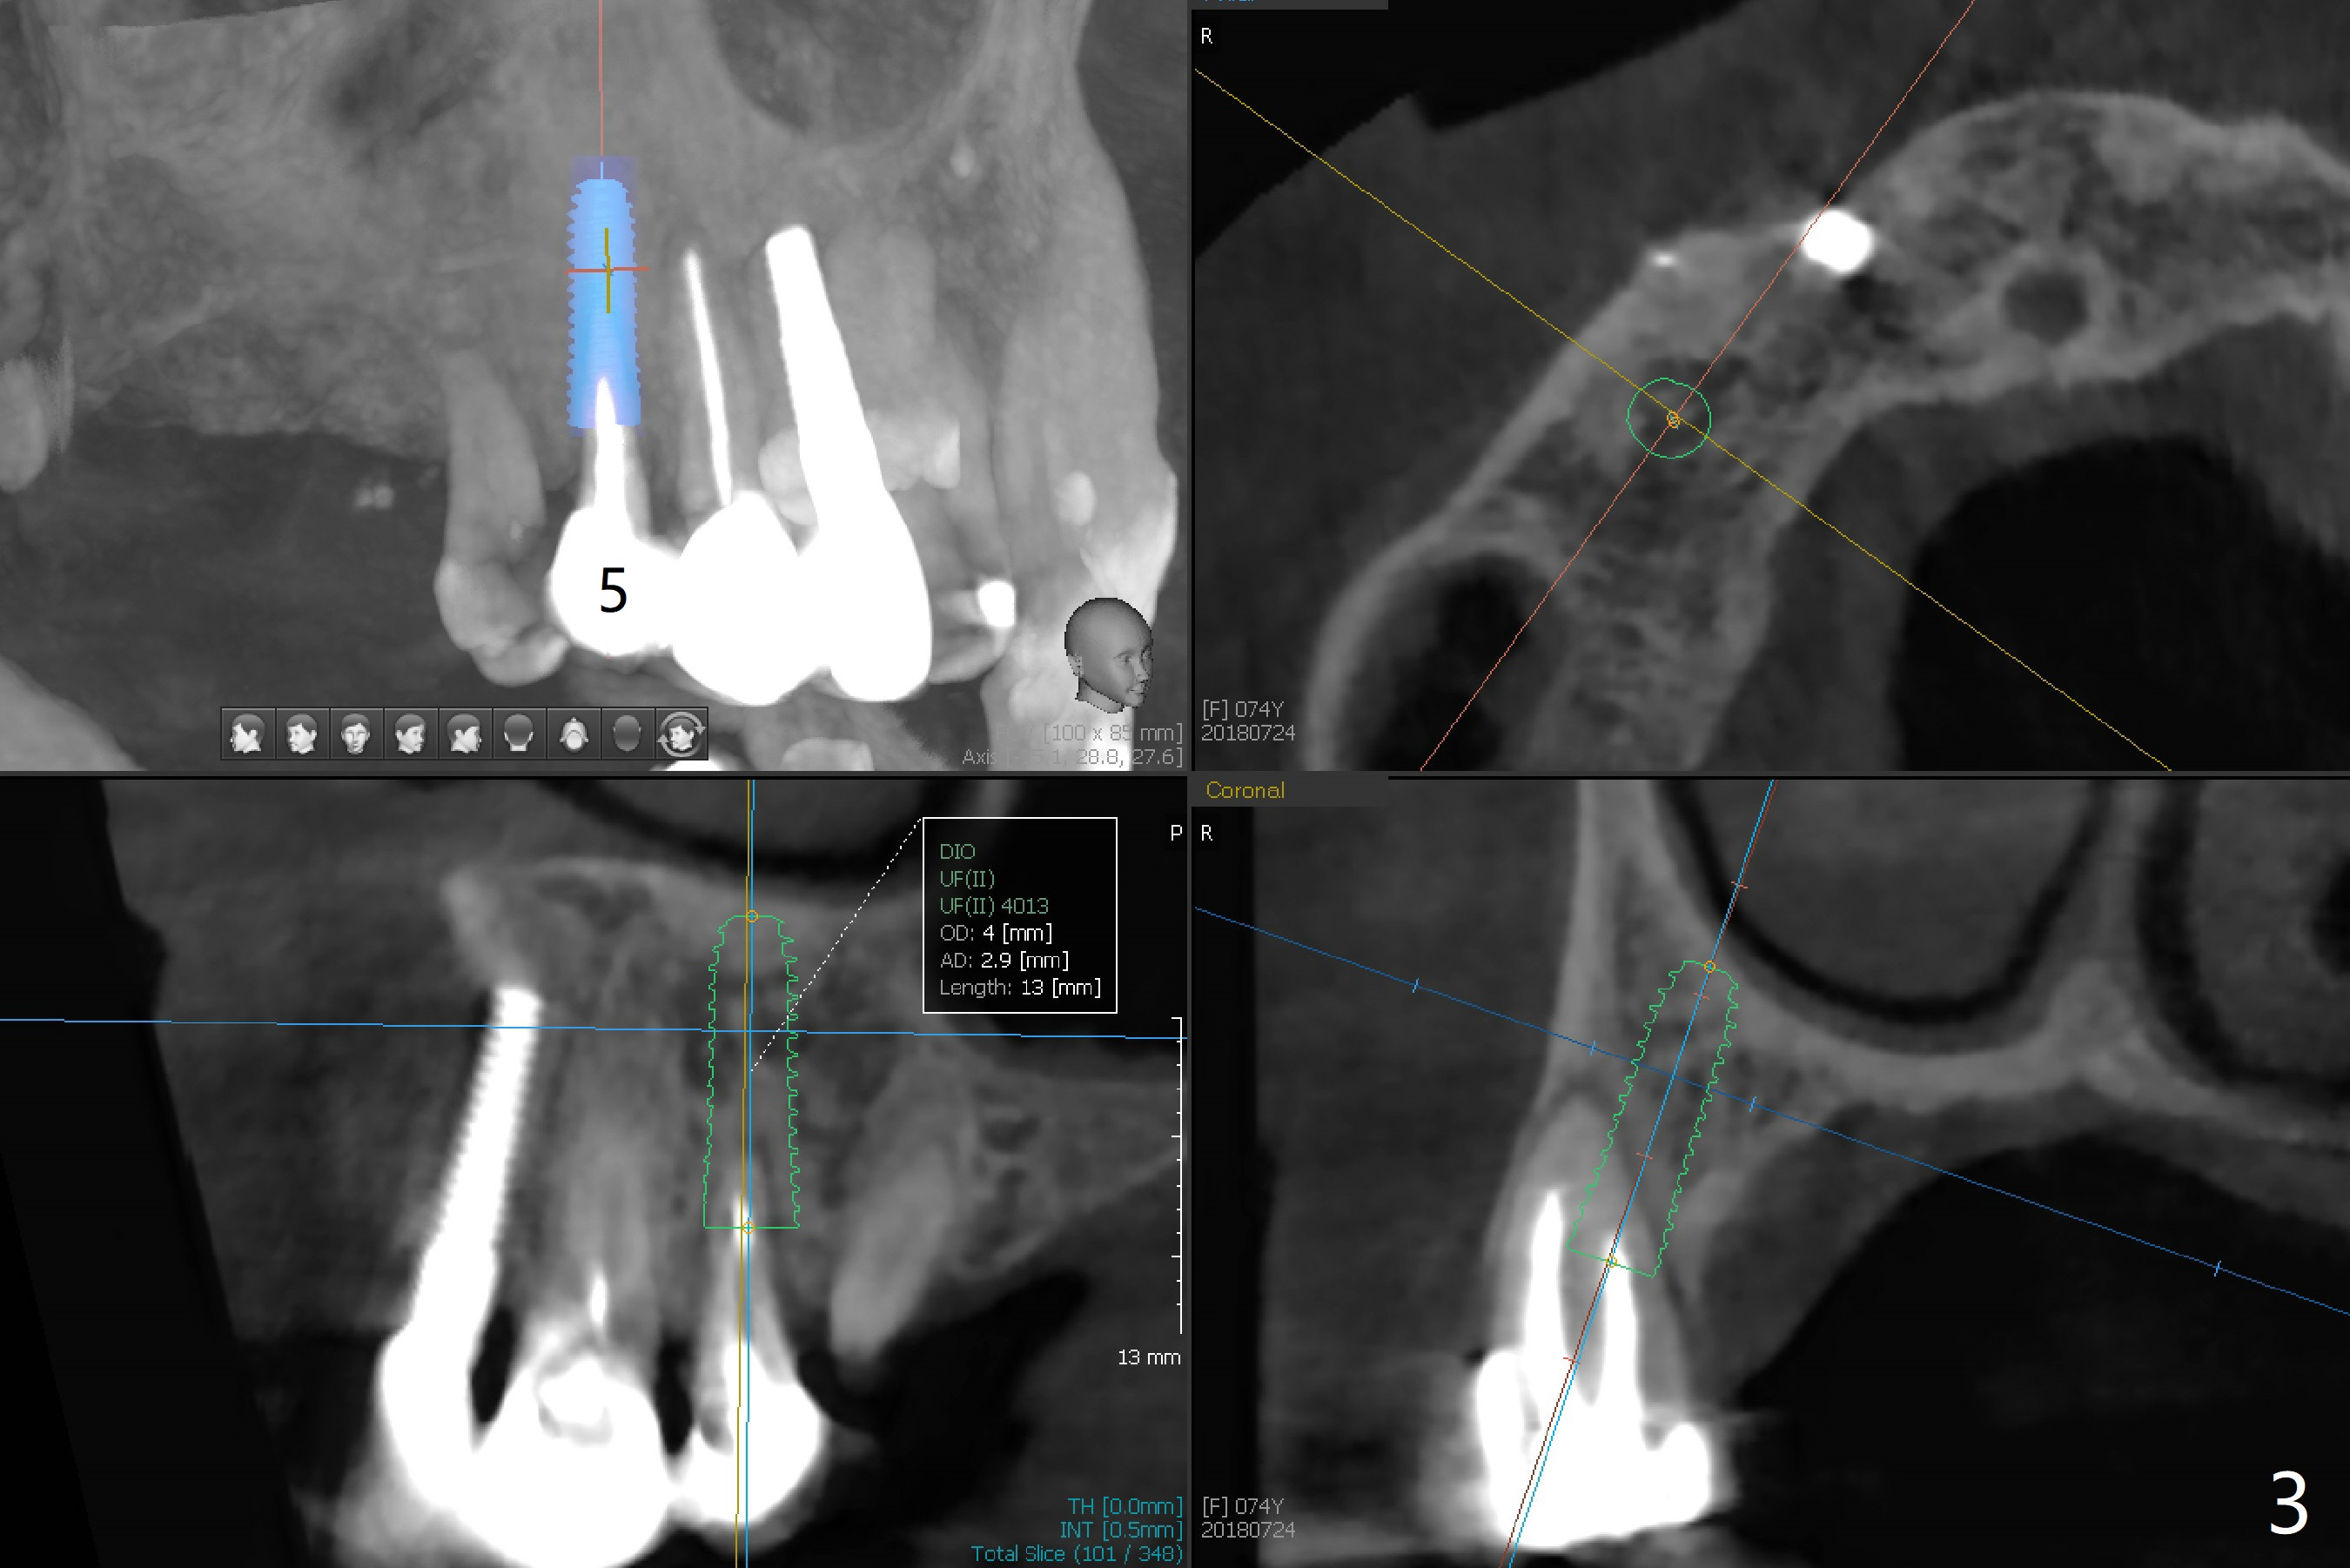

A 74-year-old woman requests treatment for a loose, tender tooth in the upper right quadrant (Fig.1). It may be due to occlusal trauma from the opposing implant tooth (Fig.2 arrow) and endo failure (Fig.2 coronal section). Because of history of low bone density and buccal placement at #7 with low primary stability, a small diameter implant will be placed palatally at #5. Either a 4x13 mm bone-level (Fig.3) or 4x17 mm tissue-level implant will be placed.